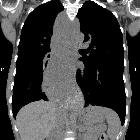

CT

Patients with uncomplicated achalasia demonstrate a dilated, thin-walled esophagus filled with fluid/food debris.

Overall, CT has little role in directly assessing patients with achalasia, but is useful in assessing common complications. Careful assessment of the wall of the esophagus should be undertaken to identify any focal regions of thickening which may indicate malignancy. The lungs should be inspected for evidence of aspiration.